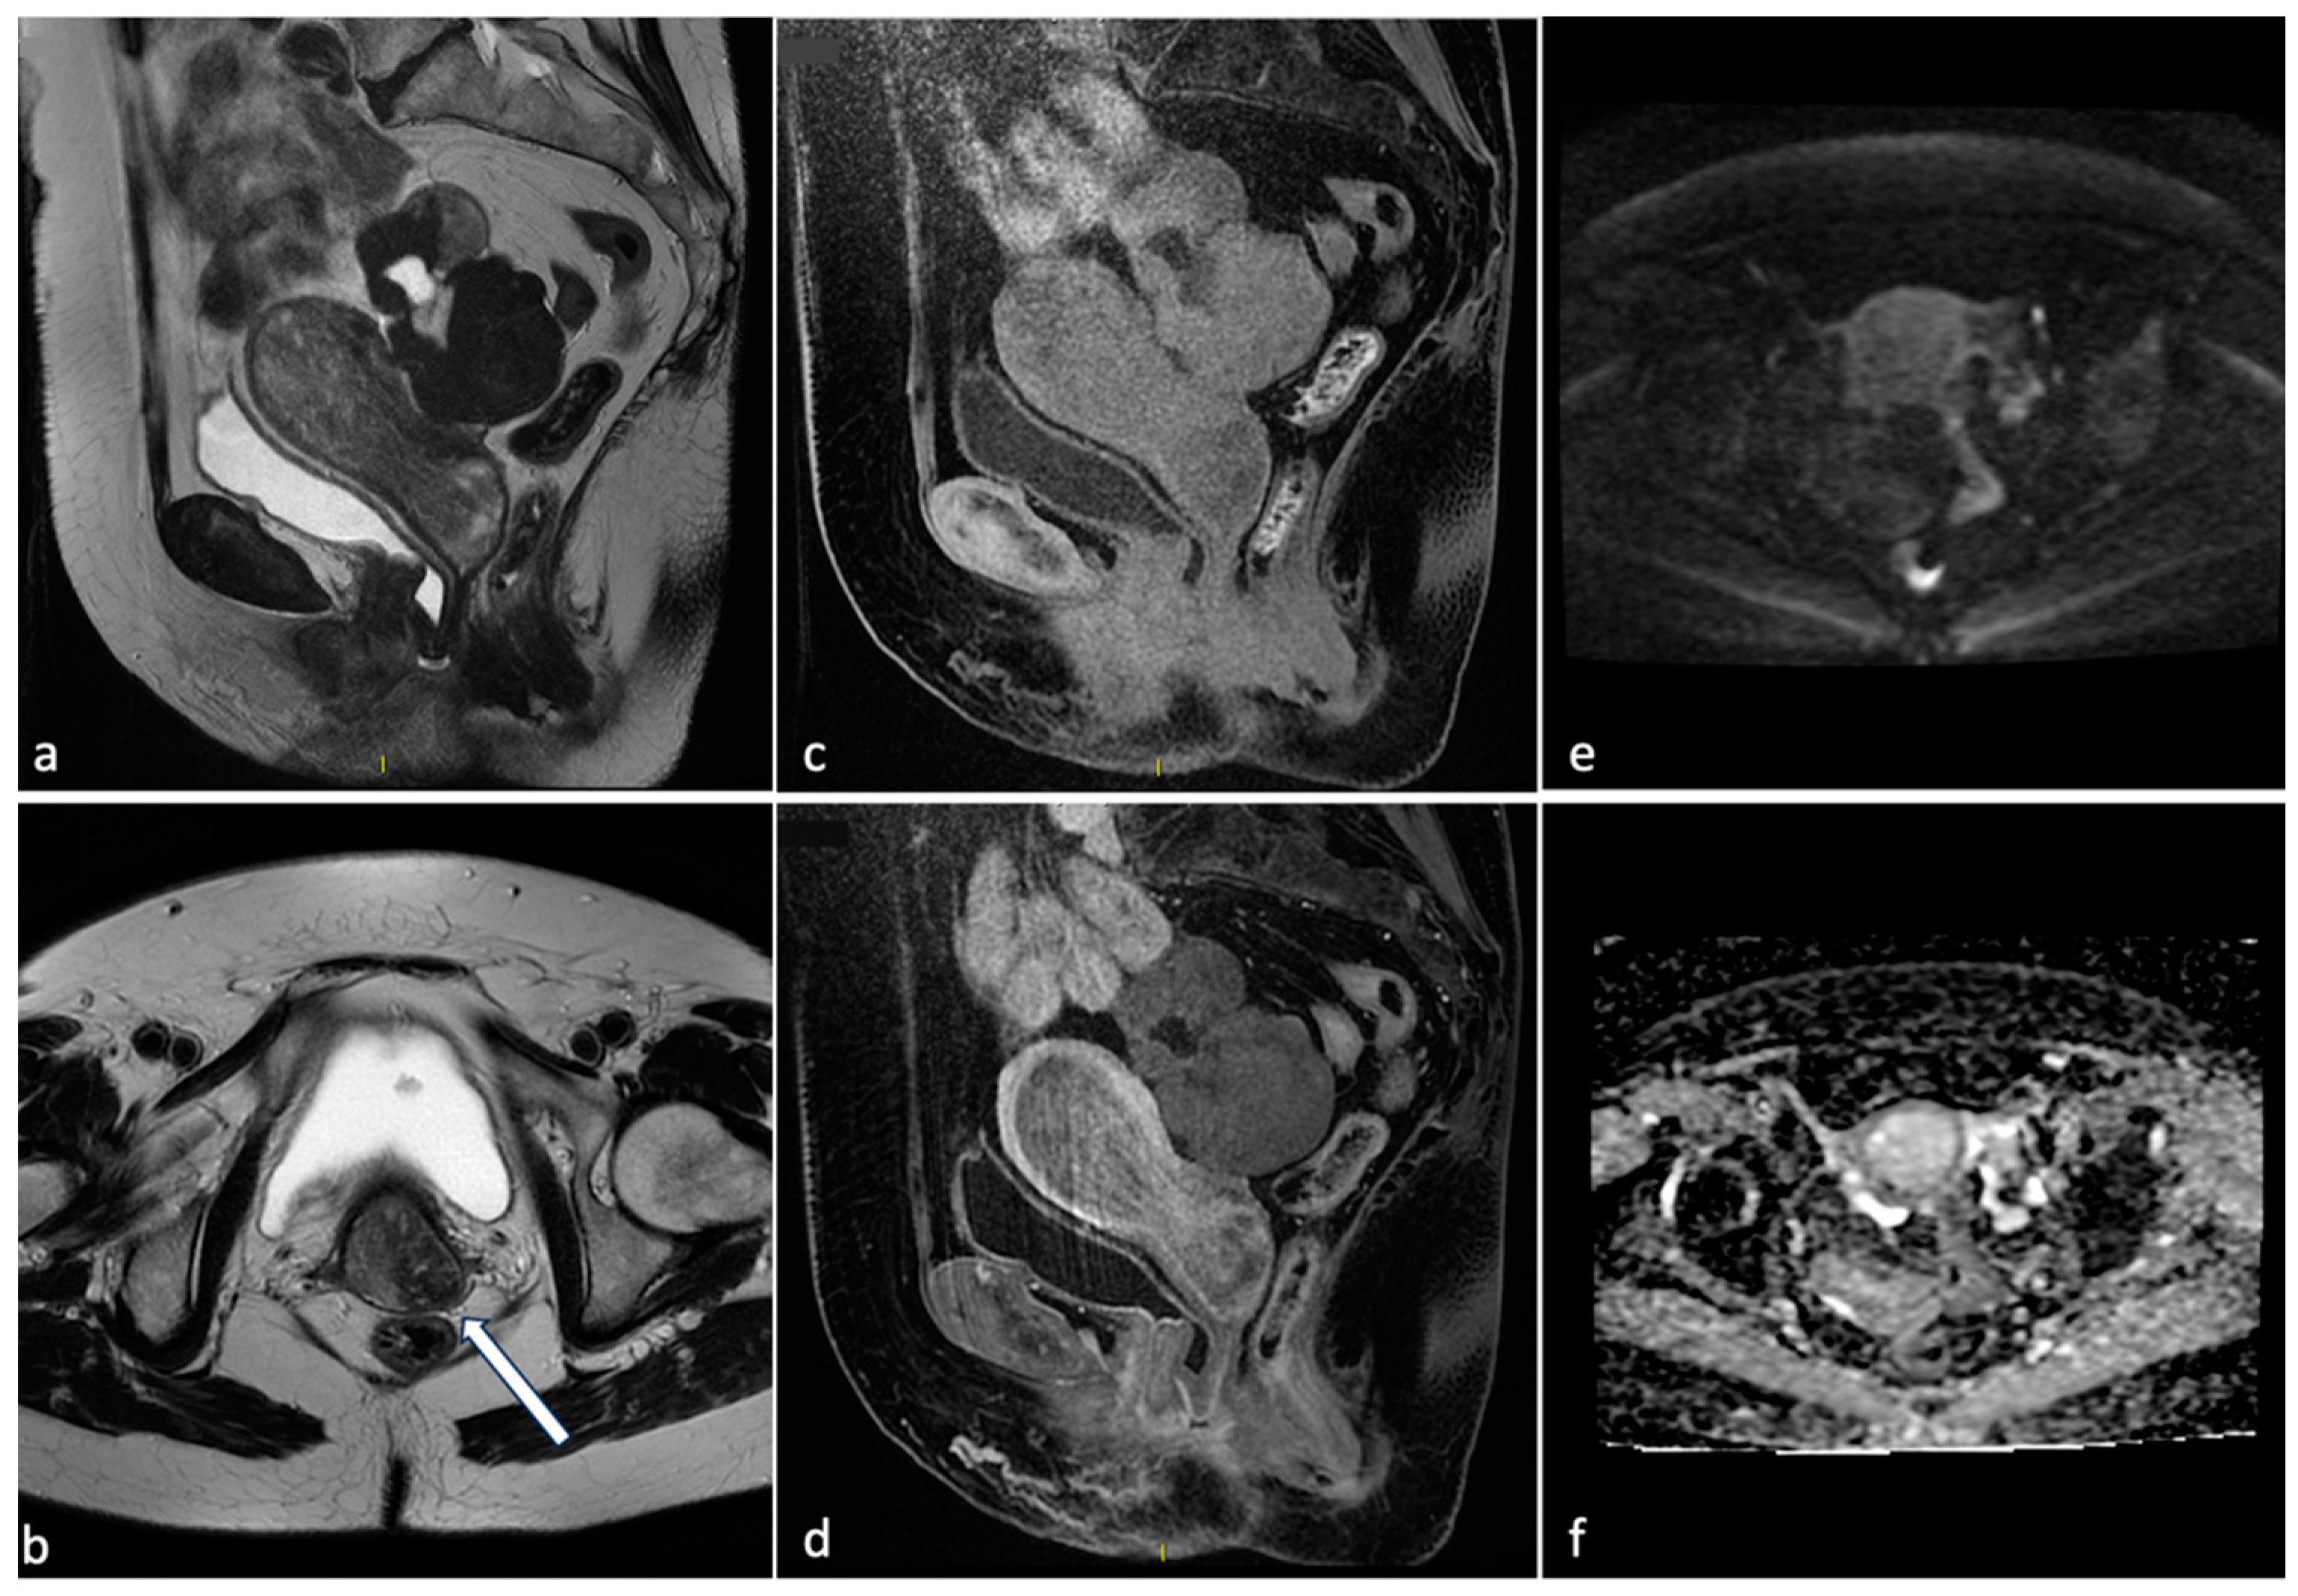

Figure 3.

Leiomyoma with red degeneration. A 43-year-old woman with known submucosal myoma with recent onset of AUB and pelvic pain. On MRI, T2 axial (a) and coronal (b) sequences show enlargement of the known submucous leiomyoma with inhomogeneous signal intensity and peripheral rim hypointensity. The leiomyoma is characterized by signal hyperintensity on T1WI (c, arrow) and a small enhancing solid portion on post-contrast T1WI (d, arrow). There is no significant restricted diffusion/hypointensity on the ADC map (e,f).